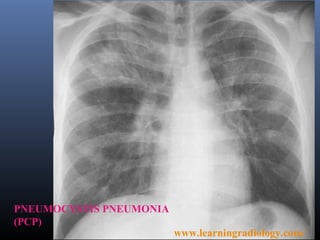

PNEUMOCYSTIS PNEUMONIA

(PCP)

www.learningradiology.com/

PNEUMOCYSTIS         PNEUMONIA (PCP)

 The most common opportunistic infection

in advanced AIDS (80% of AIDS patients

have at least one episode).

 Now considered a fungus (P.jurovecii).

 Multiple infections are often present

simultaneously with the PCP.